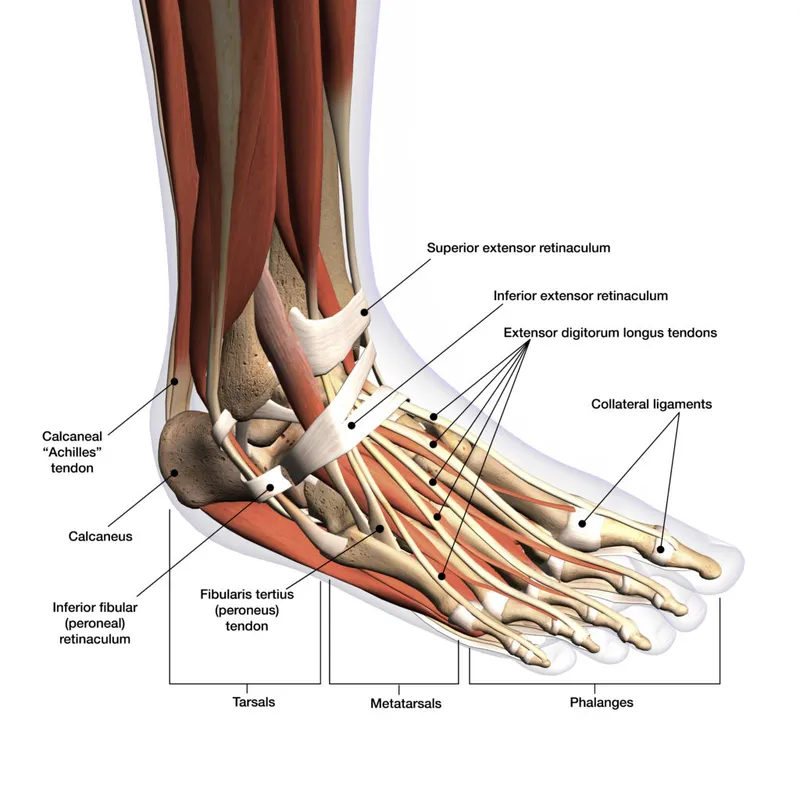

The foot functions as three integrated units: the hindfoot (talus and calcaneus), midfoot (navicular, cuboid, and cuneiforms), and forefoot (metatarsals and phalanges). This tripartite division guides surgical approaches and determines weight-bearing restrictions post-operatively.

The ankle joint proper involves three bones forming a mortise-and-tenon configuration. The tibial plafond and fibular malleolus create a socket receiving the talar dome. Normal ankle dorsiflexion ranges 15-20° while plantarflexion achieves 45-50°. Surgical restoration must preserve these ranges to prevent compensatory deformities.

The longitudinal arch system comprises medial, lateral, and transverse components. The medial longitudinal arch bears 80% of body weight and includes the calcaneus, talus, navicular, cuneiforms, and first three metatarsals. Plantar fascia tension provides 60% of arch support, while the posterior tibial tendon contributes 25%.

📌 Remember: "LAMP" for lateral ankle ligament complex - Lateral talocalcaneal, ATFL, CFL, PTFL (Anterior talofibular, Calcaneofibular, Posterior talofibular). ATFL tears occur in 85% of ankle sprains, while CFL involvement indicates Grade III injury requiring 6-8 weeks immobilization.

Understanding this foundational architecture enables precise surgical planning where each intervention must preserve or restore the delicate balance between stability and mobility that defines normal foot function.